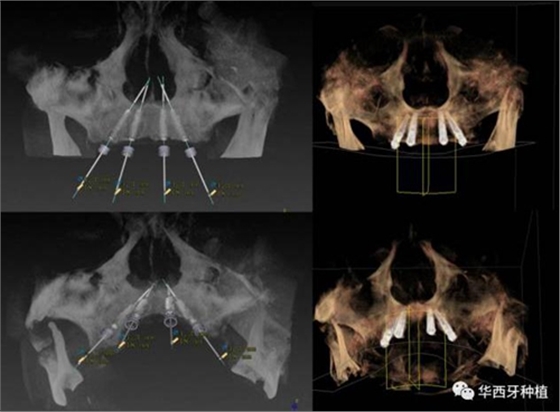

吳教授特別針對手術(shù)難度更大的all-on-four修復(fù)做了詳細的關(guān)于概念、設(shè)計、操作、修復(fù)的描述,首先是針對難度最大的手術(shù)環(huán)節(jié),就解剖、微創(chuàng)操作分別加以闡述。將他自己在臨床工作中的寶貴經(jīng)驗分享給了大家。

對于傳統(tǒng)的all-on-four術(shù)式,吳教授加入了微創(chuàng)的指導思想,設(shè)計時同樣加入數(shù)字化三維重建與修復(fù)一體化設(shè)計,增加了手術(shù)的可控性,同時極大減輕了患者的創(chuàng)傷程度,縮短了修復(fù)周期。

演講結(jié)束前,吳教授再次提到了數(shù)字化對口腔全口牙缺失種植修復(fù)一體化的重要性,構(gòu)建一體化的數(shù)字化種植修復(fù)流程,不僅能輔助手術(shù),更是簡化修復(fù)和確保遠期療效的一把利器。